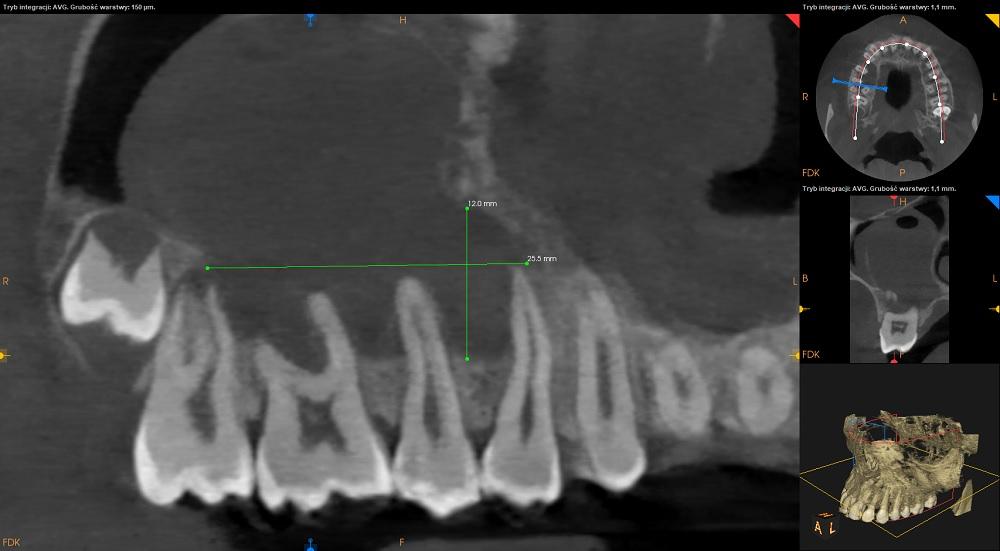

Tomografia szczęka.

Zatoka szczękowa prawa patologicznie zmieniona. Zatoka niepowietrzna w około 80% swojej objetości.

Regularny kopułowaty kształt zacienienia oraz obecność rąbka kostnego na górnej powierzchni zacienienia sugerują zębopochodne pochodzenie zmiany.

Ubytek w ścianie przedniej zatoki szczękowej prawej.